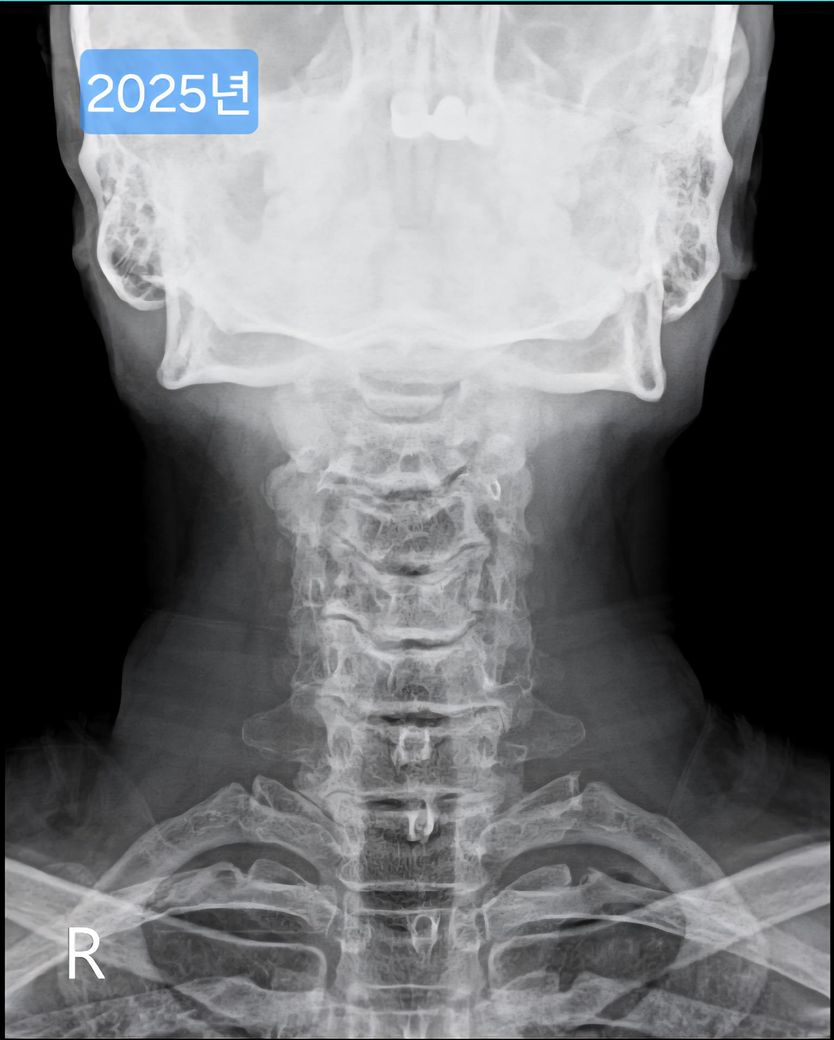

선생님이 같이 찍힌 목사진을 보시더니 심각하다며..경추사이 간격도 좁고, 일자목이고..

며칠전 찍은 2025년도 엑스레이와 9년전 사진을 업로드 해 드리겠습니다.

(이미지에 좌측상단에 해당연도 표시했습니다.)

• 2번 째 사진